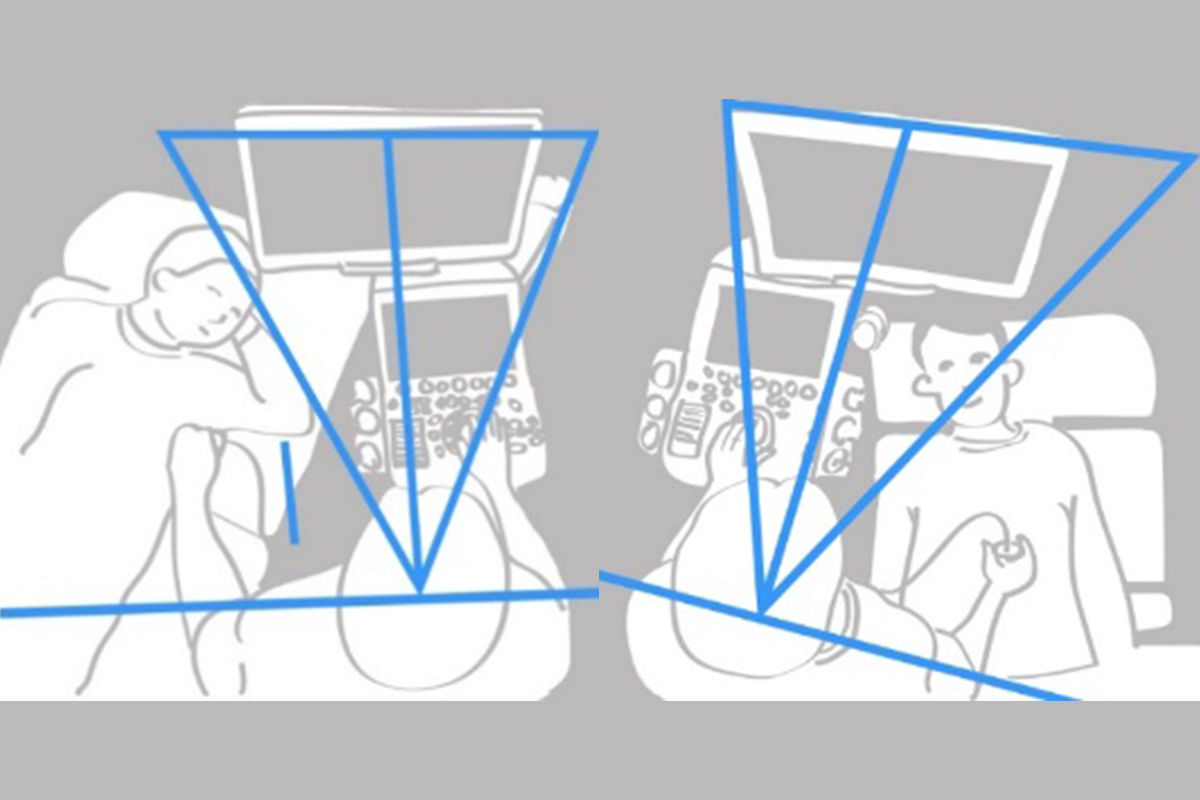

Addressing Sonographer Injury

Healthy Sonographer Platforms